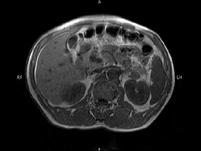

问题 男,52岁,下肢无力伴多饮多尿2?年余,实验室检查:低血钾,血醛固酮水平及24小时尿醛固酮定量超过正常值,MRI检查如图所示,应诊断为()

选项 A.左肾上腺囊肿 B.左肾上腺腺瘤 C.左肾上腺嗜铬细胞瘤 D.左肾上腺髓脂瘤 E.左肾上腺转移瘤

答案 B